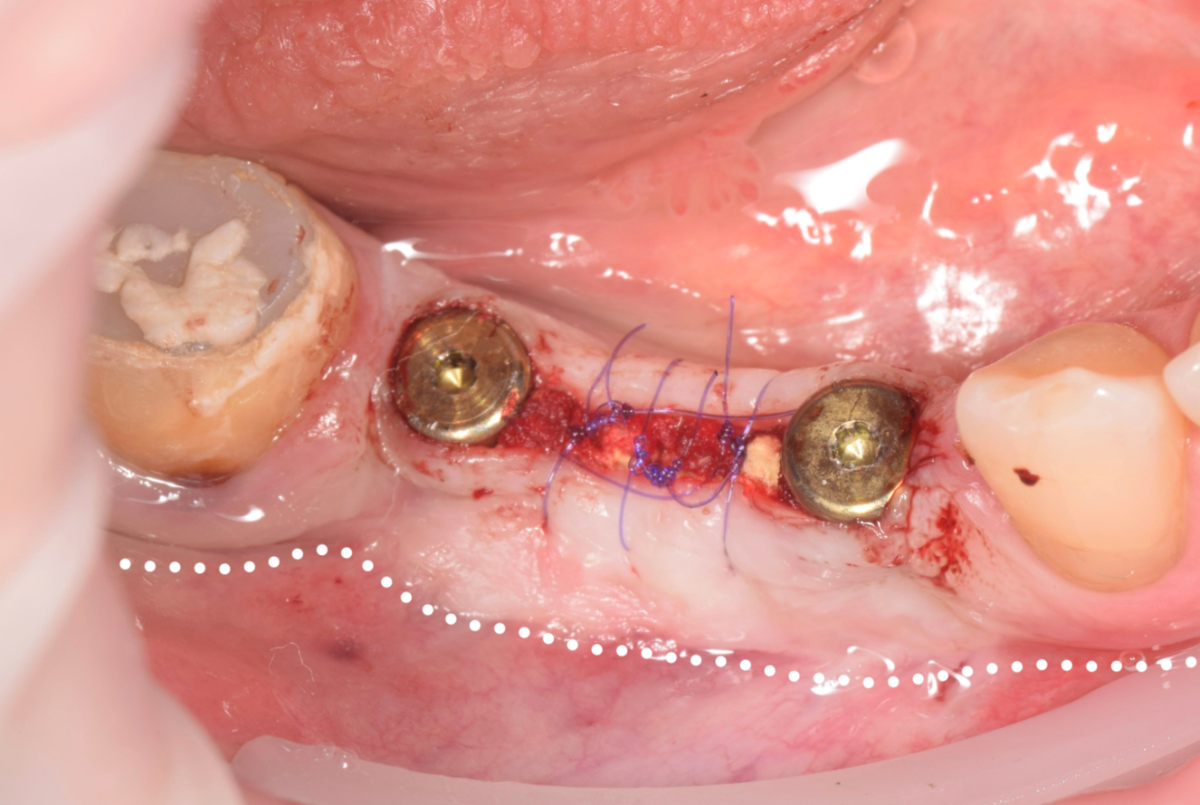

Fin Опубликовано 5 июня, 2025 Поделиться Опубликовано 5 июня, 2025 Здравствуйте коллеги. Хотел бы представить вашему вниманию первую часть кейса по восстановлению 4 сегмента. Перелом зуба 4.5 под мостовидным протезом 4.7-4.4. 4.7 решено оставить до последующего повторного протезирования При планировании имплантации вестибулярное оголение имплантата на 1.5-2мм в области 3. 4. Дефицит керотинизированной слизистой оболочки. Более глубокое положение имплантата приведет к чрезмерному количеству сзизистой оболочки в 7-8 мм. Решено не пытаться использовать ССТ с целью перекрытия оголенного имплантата а попробовать технику морковки профессора Кюри. 1 этап операции. Удаление зуба 4.5, подготовка костного ложа под имплантаты при помощи трепанов и запор костных морковок, установка имплантатов неодент 3.75х10 в позицию 4.4, 4.3х10 в позицию 4.6, ушивание. 2 этап. Создание прикрепленной слизистой. Расщепление лоскута, удаление пиноа, пересадка СДТ с фиксаций его этими же пинами. 3 этап. Открытие имплантатов с установкой ФДМ и снятие швов через 2 недели. Решил не добавлять ССТ. На данный момент ожидаем полное восстановление тканей и приступаем к этапу протезирования. Так как параллельность имплантов достаточна планирую протезировать с уровня имплантатов. 3 2 1 Ссылка на комментарий